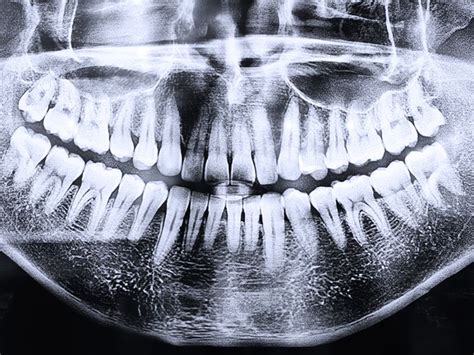

Se toman radiografías para obtener una visión completa de las estructuras internas. Entre ellas se encuentran:

- Ortopantomografía (Radiografía Panorámica): Es una radiografía frontal, en la que se obtiene una imagen general de los dientes y los huesos maxilares (maxilar superior y mandíbula). Esta prueba es importante ya que gracias a ella podemos conocer el estado de las raíces de los dientes, el tejido óseo, las coronas… En definitiva, nos ofrece una información que a simple golpe de vista o pese a un estudio visual más pormenorizado no podrías ni tan siquiera vislumbrar.

Radiografía panorámica dental.